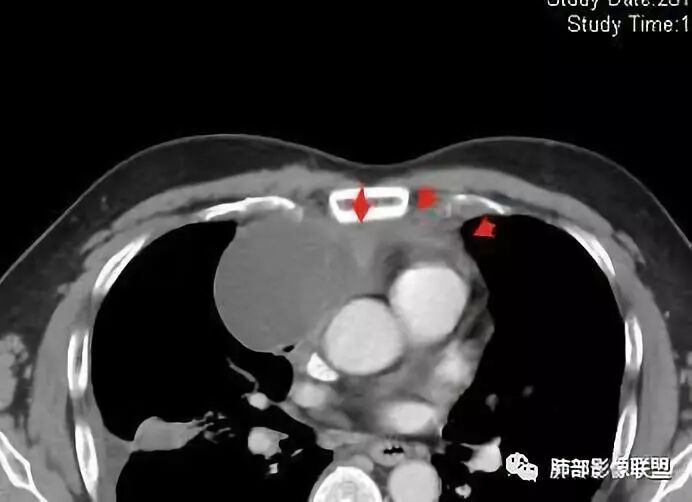

南边:大家看看前纵隔的病灶,符合肿瘤吗脂肪,周围密度增高

三个石头:比较散;像炎症的蔓延生长南边:是,这些看着心里不踏实觉得把这个纳入肿瘤去考虑是否合适总觉得边缘收缩的、散在的朝周围蔓延;中央还跨过脂肪,朝对侧胸膜蔓延把这个与囊性病变连到一起去考虑是否还需要斟酌一下因为这个就方向差异大了南边:连在一起,囊实性,边界不清,自然考虑恶性:如果独立,囊张力高、边界清楚,间隔,自然朝良性考虑:

Coke with ice:囊性部分考虑包裹性积液?南边:不是积液;有间隔;张力高;而且位置有些特殊

大家仔细看看积液中的游离气体;

不是支气管,是积气;是穿刺进去的;

我认为囊张力高,积液中的气体均在周围,外侧、下方,囊内有间隔:各腔密度不一致;提示:囊腔属于前纵隔,不是包裹性积液;现在的问题:囊腔与内侧的病灶是否是一体的

南边:我总觉得这个纵隔内不像是一个肿块的改变,扁平,周围蔓延:有符合炎性的的特点,或者肿瘤的侵犯;但是肿瘤的侵犯,不大符合,实性部位的边缘过于柔和,没有毛糙的侵犯边缘。

南边:纵隔囊性病变:良性?恶性:胸腺癌?

2、前纵隔内病灶囊实性混杂密度病灶,囊性病灶主要位于右侧,张力较高,有分隔影,囊壁右侧缘光整,病灶左侧实性部分边界不清明显强化,病灶肺瘤交界面大部分边界清楚,部分模糊。

前纵隔肿块伴囊变坏死常见以有胸腺瘤、胸腺癌、淋巴瘤和生殖细胞肿瘤。

胸腺瘤/胸腺癌:病灶内那么大的囊,常规考虑B型以上胸腺瘤,囊内有分隔影,病灶周围脂肪间隙模糊,常规考虑侵袭性胸腺瘤或胸腺癌,若侵袭性胸腺瘤,常侵犯胸膜、心包,很少累及肺。胸腺癌易侵犯胸膜、肺并纵隔淋巴结及远处转移。但肺内腺癌形态更符合原发灶。胸膜及叶间裂转移则即可来自肺,也可来自胸腺癌。